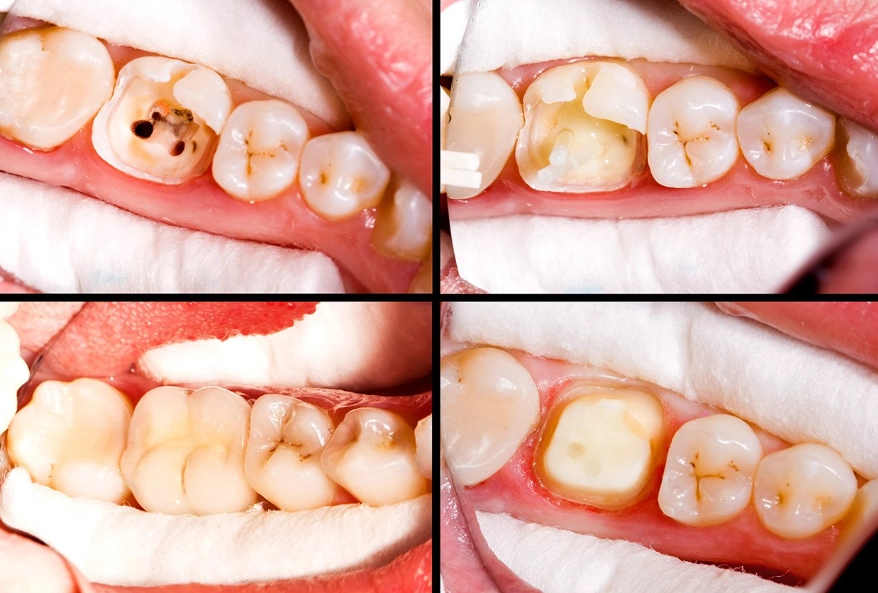

At its core, a root canal treatment on a premolar is a procedure to remove infected or inflamed pulp—the soft tissue inside your tooth containing nerves and blood vessels. Once that's gone, the inside of the tooth is cleaned, disinfected, and sealed. Think of it like removing the spoiled wiring from a house and filling the space with a stable, inert material. The goal is to eliminate pain, stop the spread of infection, and allow you to keep your natural tooth structure. The alternative, pulling the tooth, creates a whole new set of problems like bone loss and shifting teeth, which are costlier and more complex to fix down the line.

Not all teeth are created equal. Premolars, also called bicuspids, are the teeth between your canines and molars. You have eight of them. Their job is a hybrid: they help with tearing food like canines and grinding it like molars. This dual role makes their anatomy a bit of a wild card.

Here's the part most blog posts gloss over, and it's the single most important factor for long-term success: the final restoration. A root canal-treated premolar is more brittle than a vital tooth. It's like a hollowed-out tree branch—structurally weaker.

That temporary filling is just that—temporary. Leaving it in place for months is asking for trouble. The tooth can crack under normal chewing forces, and then it's unsalvageable. I've seen it too many times.

For almost every premolar, you will need a dental crown. This cap encases the entire tooth, protecting it from fracture and restoring its function for chewing. Sometimes, if a lot of tooth structure is missing, a post may be placed inside the canal to help anchor the crown. Don't delay this step. Schedule your crown appointment within a few weeks of the root canal.